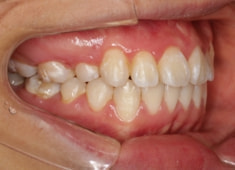

治療後(2年後)